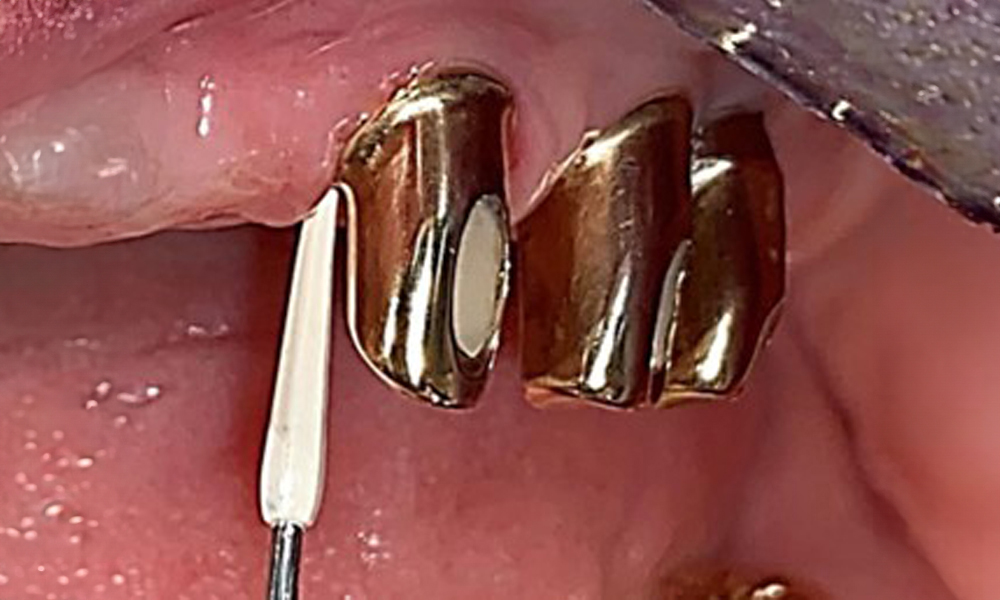

Frontalansicht mit dem eingesetzten Zahnersatz im Oberkiefer.

Abb. 1: Frontalansicht mit dem eingesetzten Zahnersatz im Oberkiefer.

Die Patientin wurde vor über 25 Jahren mit einer kombinierten herausnehmbare Implantat-Teleskopprothese im Oberkiefer versorgt (Abb. 1, Abb. 2, Abb. 3) und ist sehr glücklich über ihren Zahnersatz. Im Unterkiefer hat die Patientin einen suffizienten festsitzenden Zahnersatz. (Abb. 4)

Der dentale Befund stellt sich wie folgt dar: Kombinierte herausnehmbare Implantat- und zahngetragene Teleskoparbeit auf Implantaten 15, 13, 21, 23, 24, 25 und Zahn 11 (Abb. 1, Abb. 2, Abb. 3). Im Unterkiefer ist die Patientin mit einem festsitzenden Zahnersatz versorgt. 37–34 sowie 45–47 haben suffiziente Brücken (Abb. 4). Kronenränder sind intakt, aktive kariöse Läsionen sind nicht vorhanden. An Zahn 43 zeigt sich eine Compositefüllung mit Randspalt. Im Unterkiefer liegen Rezessionen mit freiliegender Wurzeloberfläche zwischen 1 – 3 mm vor. Dies trifft auch für 11 zu.